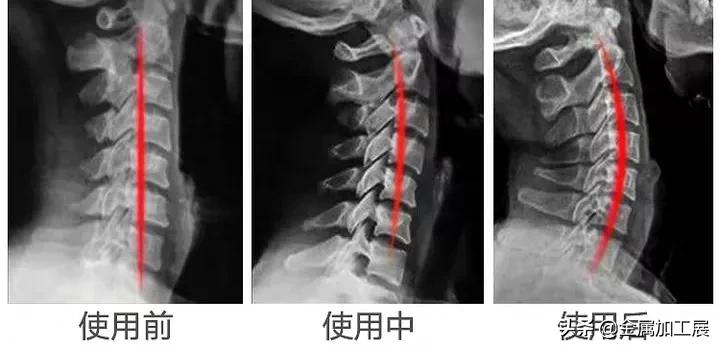

幸好,有朋友给我推荐了这款日本3T颈椎牵引枕,根据人体工学打造,每天枕30分钟,就可以牵引、纠正颈椎,让颈椎恢复正常曲度。

而这款3T颈椎牵引枕,仰卧时,头部自然下垂,与牵引枕呈45°夹角,可以感觉到它与颈椎的完美贴合,不知不觉颈椎就慢慢恢复到正常曲度。

正面3点支撑设计,更好的贴合头、颈、肩,利用头部自身重力牵引拉伸,帮助恢复颈椎正常生理曲线的同时,也让颈椎一天比一天放松。

在颈椎牵引枕的反面,采用多点分压设计,利用头后部、颈、肩不同重力作用下的纯物理性进行反向轴转向的牵引。